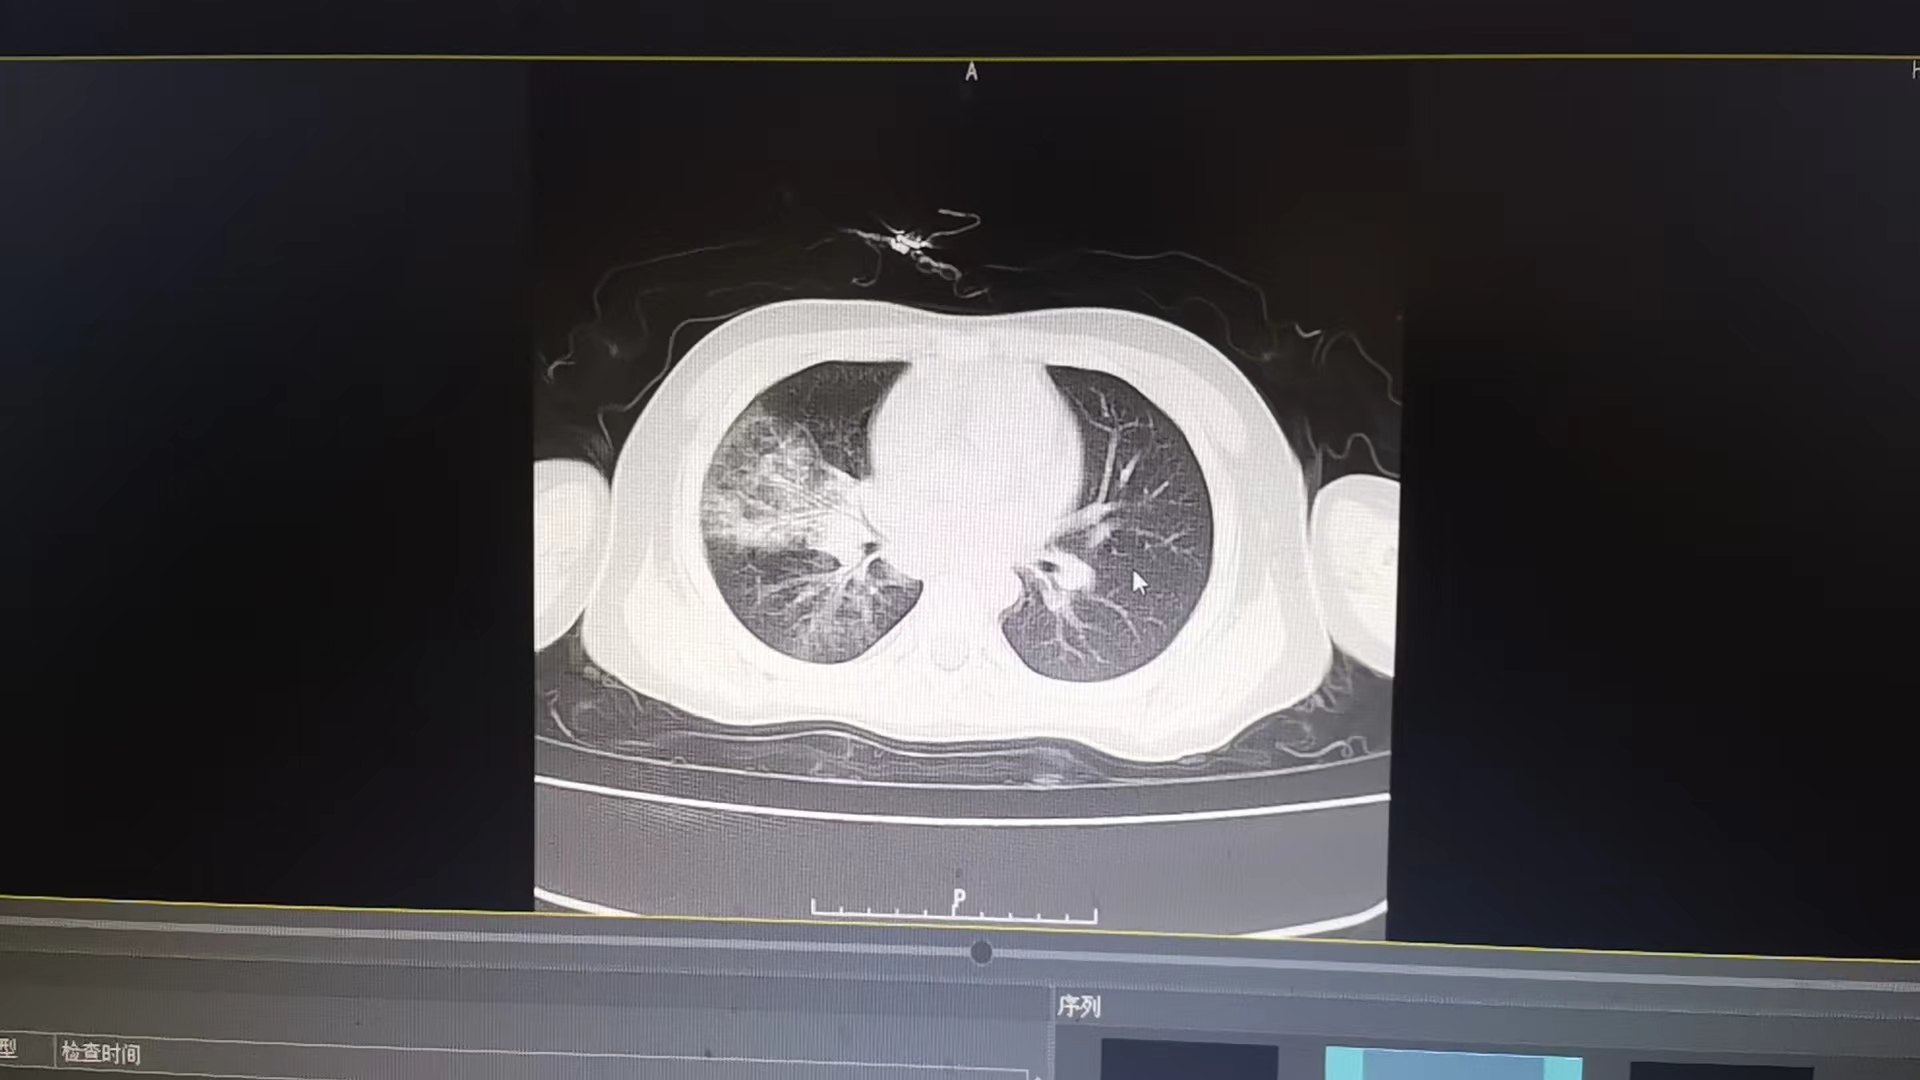

患儿陈某,咳嗽发热3天后到娄底市第二人民医院儿科就诊,经诊断,为右下肺大叶性肺炎。大叶性肺炎发病比较急骤,如果不及时治疗可能引起肺外感染或出现全身中毒症状。该科立即予以抗感染,化痰平喘及雾化治疗配合儿科特色中药肺炎敷贴,治疗6天后复查明显好转,再行巩固治疗后症状消失,肺部呼吸音恢复正常出院。

大叶性肺炎患者治疗前肺部CT